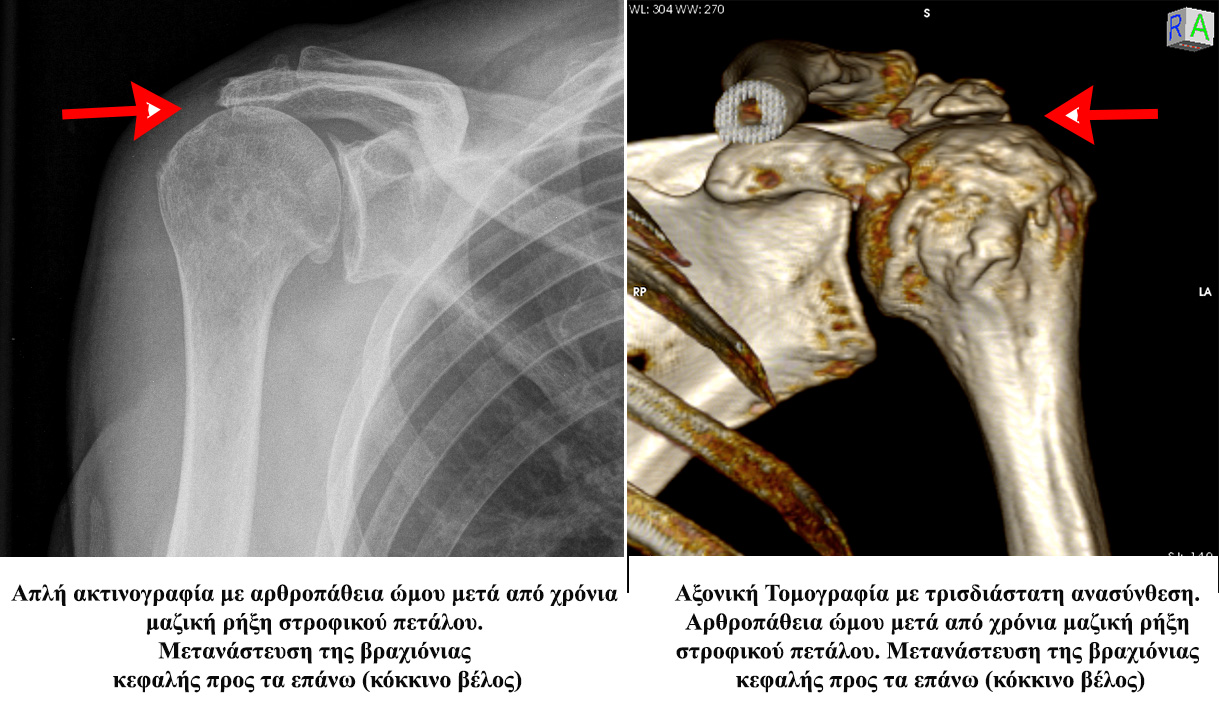

Τελικά μερικές χρόνιες ρήξεις καθίστανται μη διορθώσιμες-μη συρράψιμες ενώ παράλληλα η κεφαλή του βραχιονίου μεταναστεύει προς τα επάνω- προς το ακρόμιο αναπτύσσσοντας βλάβες του αρθρικού χόνδρου

(Αρθροπάθεια- Rotator cuff arthropathy)